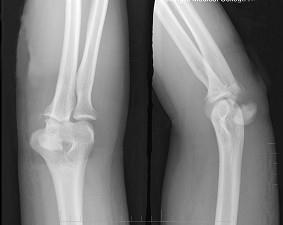

男,38岁,右肘关节外伤,请结合所提供图像,选择最佳答案 ( )A、肘关节脱位B、未见异常C、鹰嘴骨折D、肱骨内侧髁骨折E、肱骨外侧髁骨折

选项 A、肘关节脱位 B、未见异常 C、鹰嘴骨折 D、肱骨内侧髁骨折 E、肱骨外侧髁骨折

答案 C